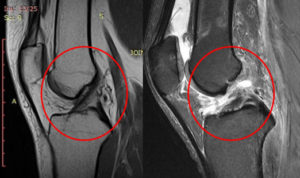

- МРТ. Также весьма эффективным методом является магнитно-резонансная томография. При её проведении используются электромагнитные волны, которые позволяют визуализировать не только плотные, но и мягкие материи. Благодаря этому можно отследить разновидность травмы.

Магнитно-резонансная томография позволяет увидеть все повреждения сустава, в том числе крестообразных связок, в 3d проекции.